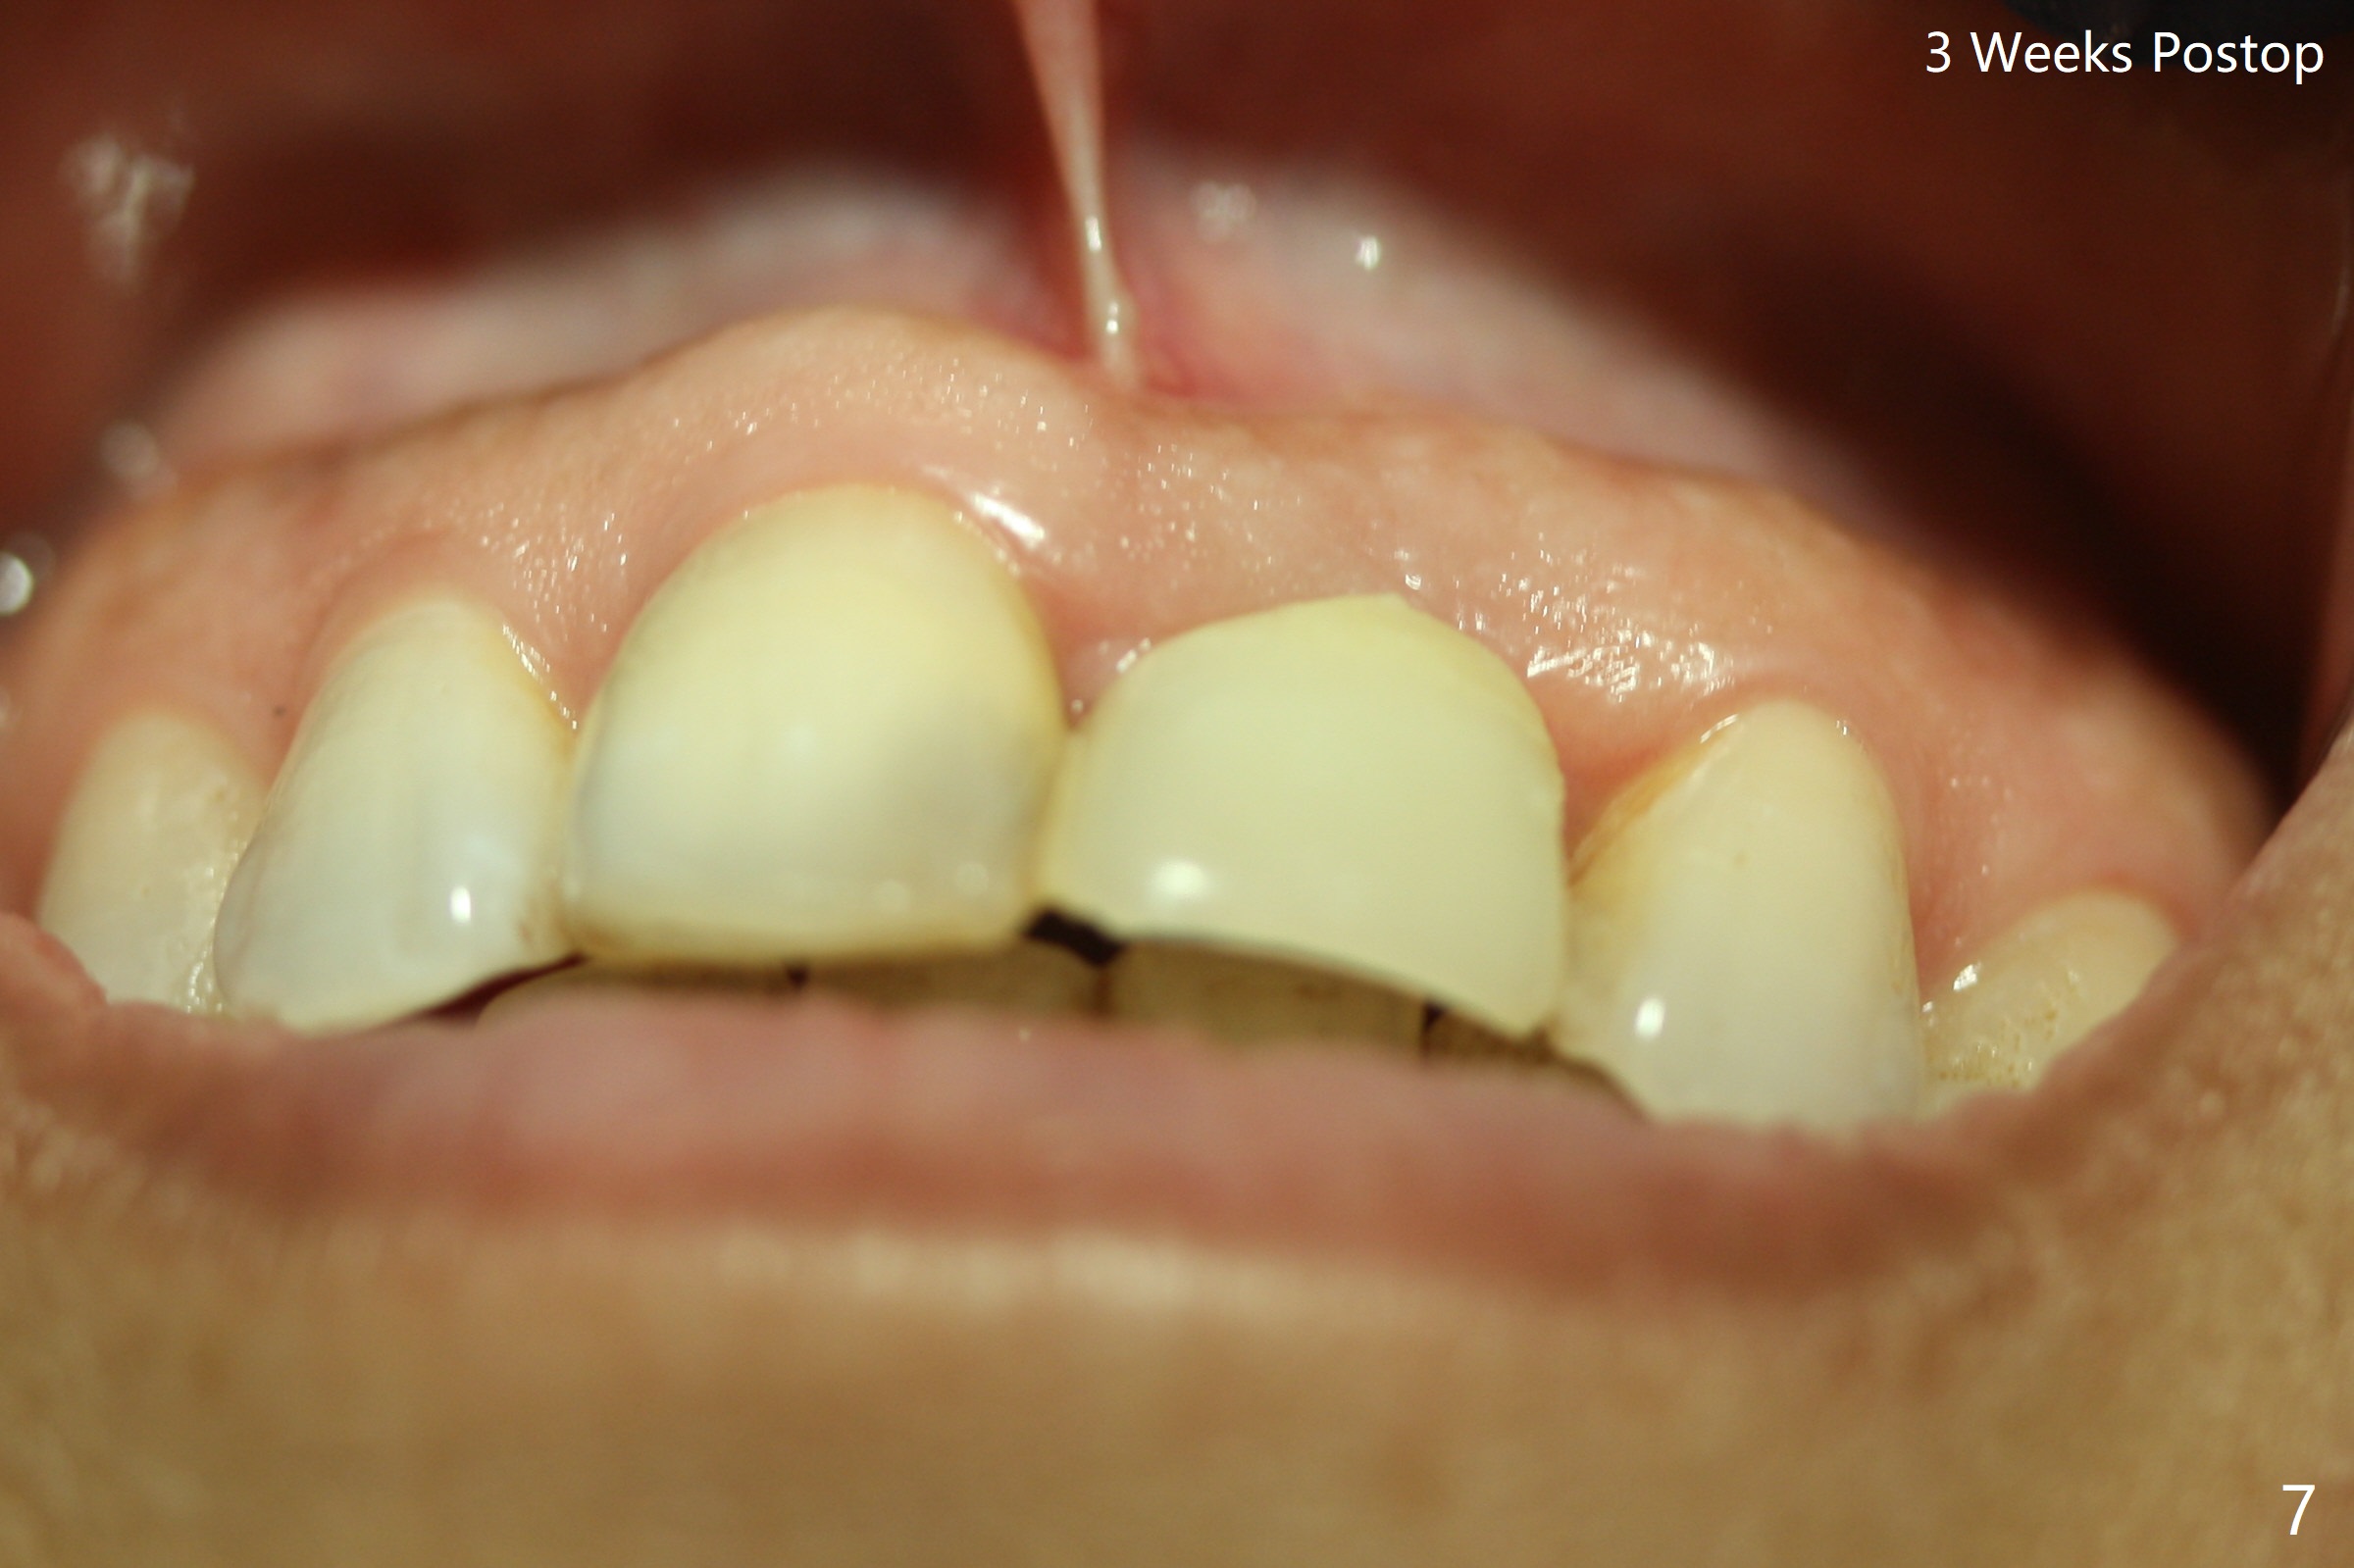

Except the depth, a 2.5x10 mm mini implant is placed with precision (in trajectory) at #9 (Fig.1-5). Confidence using surgical guide for the narrow ridge is enhanced due to placement of two digits against the buccal and palatal plates for tactile sensation. The depth issue is related to overprep with 2.2 mm drills. The torque is <15 Ncm. The immediate provisional is bonded to the neighboring teeth for retention. It appears that smaller drills should be made for guided surgery (such as 1.5 and 2.0 mm). The immediate provisional looks acceptable buccal and occlusal 3 weeks postop (Fig.6,7), although the palatal gingiva is erythematous (Fig.8, which is common after use of drill for access (tissue laceration), OHI offered). Three months postop (Fig.9), the palatal gingiva looks healthy (data not shown), while there is no bone loss around the implant (Fig.10). It remains the same 5 months postop (immediately post cementation, Fig.11) and 3,11 months post cementation (Fig.12,13). The labial gingiva is healthy (Fig.14), while the palatal one is less erythematous and edematous (Fig.15) than earlier (Fig.8).